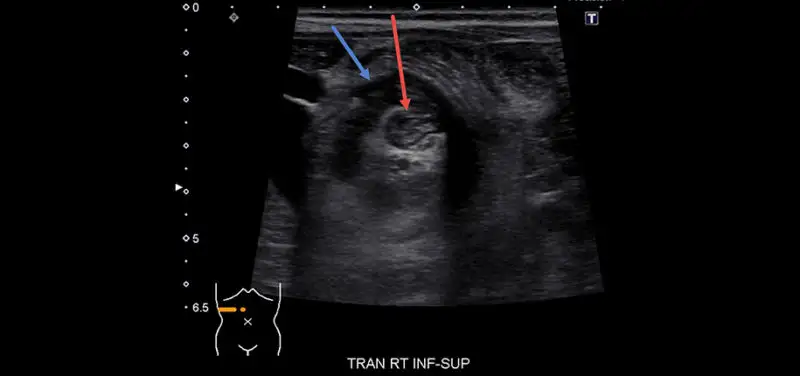

Image: Ultrasound image of intussusception. Red arrow: inside bowel loop (intussusseptum). Blue arrow: outside bowel loop, the wall is thickened from edema (intussussipiens). Image contributed by Dr. Aaron McAllister.

Intussusception is a condition in which one part of the bowel telescopes into the bowel next to it. Ileocolic intussusception is a specific type in which the small bowel telescopes into the colon. Treatment of this type of intussusception is required because the small bowel can get trapped in the colon and become injured.

The diagnosis of ileocolic intussusception is most often made with ultrasound. Once the diagnosis is made, the intussusception can be treated (“reduced”) in Radiology. Reduction of an intussusception involves inflating the colon by instilling air through a small tube placed in the rectum. As the air inflates the colon, the pressure pushes the telescoped piece of bowel out and back into normal position. The vast majority of ileocolic intussusceptions are successfully treated in this way. Surgery may be indicated in certain cases but is used much more rarely.